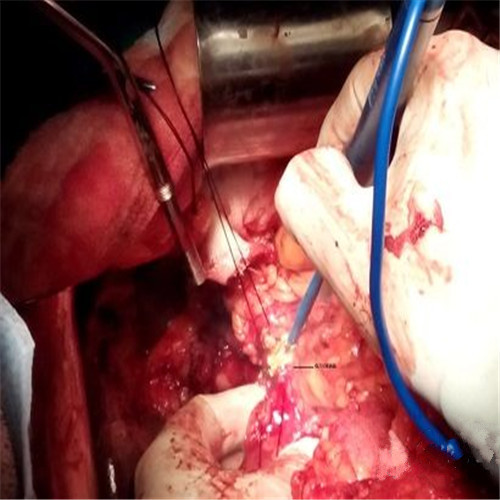

潰瘍性結腸炎微創手術